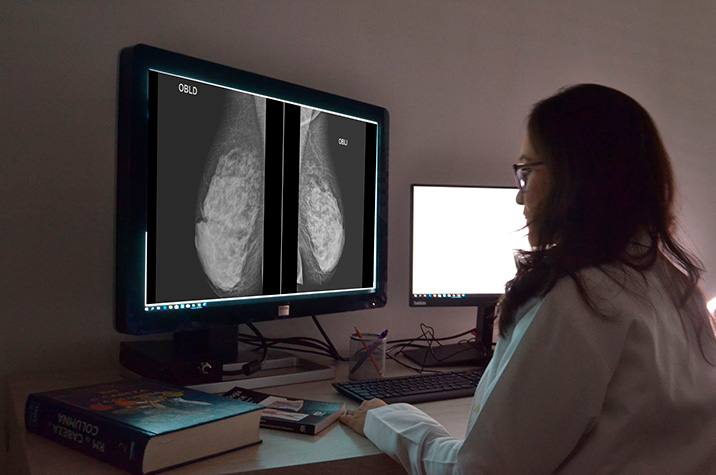

Detección del cáncer de mama mediante mamografía, tomosíntesis mamaria digital y resonancia magnética según la densidad mamaria

28 agosto 2024

En este análisis de efectividad comparativa basado en modelos, la resonancia magnética suplementaria para mujeres con mamas densas sumada al cribado con mamografía condujo a mayores beneficios y también mayores daños. El balance de esta compensación para el uso de RMN suplementaria fue más favorable cuando se dirigió a mujeres con mamas extremadamente densas que comprenden aproximadamente el 10% de la población. JAMA Internal Medicine, 26 de agosto de 2024.

Rendimiento de la resonancia magnética mamaria en el rastreo de cáncer

16 febrero 2018

En comparación con la mamografía, la resonancia duplica el número de biopsias pero con un menor rendimiento diagnóstico. JAMA Internal Medicine, 12 de febrero de 2018